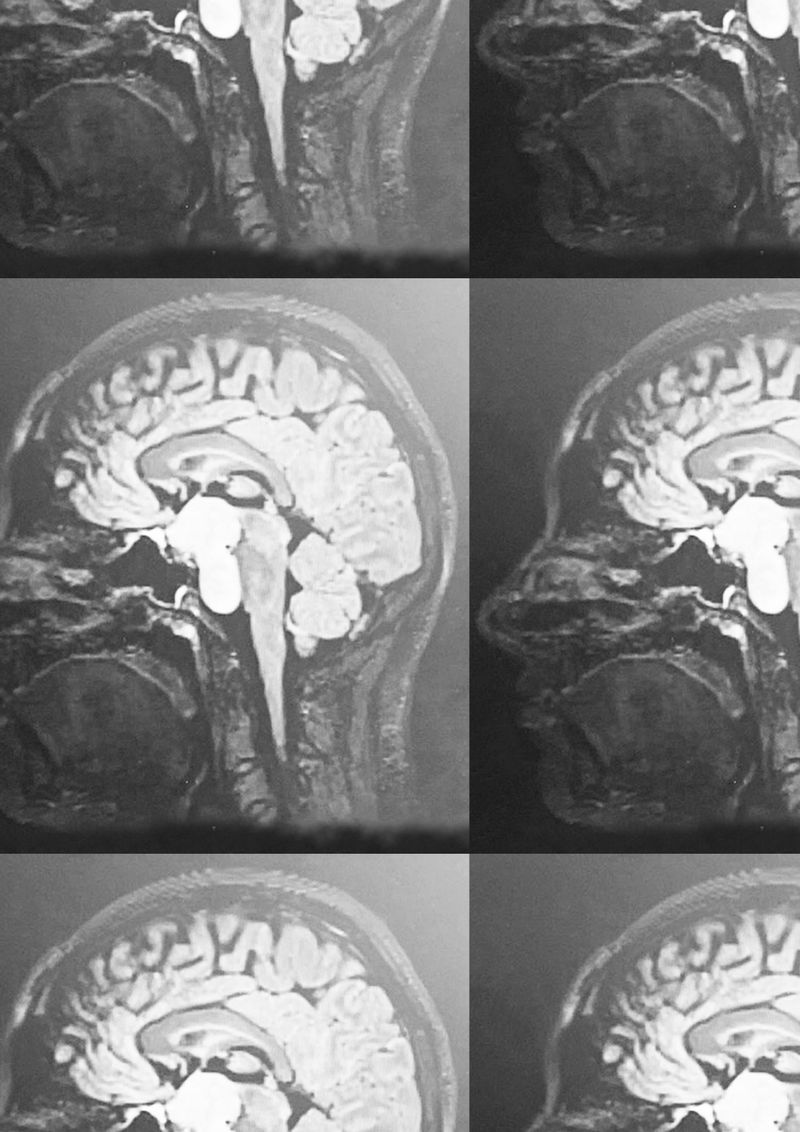

Since her early teens, Eden’s experience has been shaped by extreme hormonal challenges, compulsions, and behavioural shifts. In July 2024, an MRI revealed a large benign brain tumour in the centre of her head, assumed to have been there since childhood. Since it's size and position have made it too complex to remove, she has remained under constant monitoring and must take hormone replacement therapy for the rest of her life.